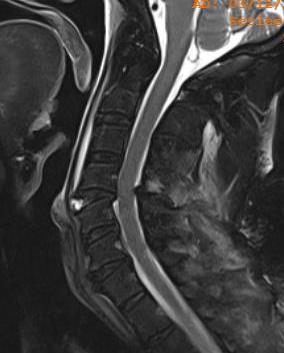

MRI

Teardrop fracture with disruption of ALL with cord contusion and disc prolapse

Anterior column fails under compression

- hearing of the anterior vertebral body

- rupture of the ALL

- disruption of the discoligamentous complex

Posterior column fails under tension

- disruption of PLL

Retrolisthesis of upper spinal column